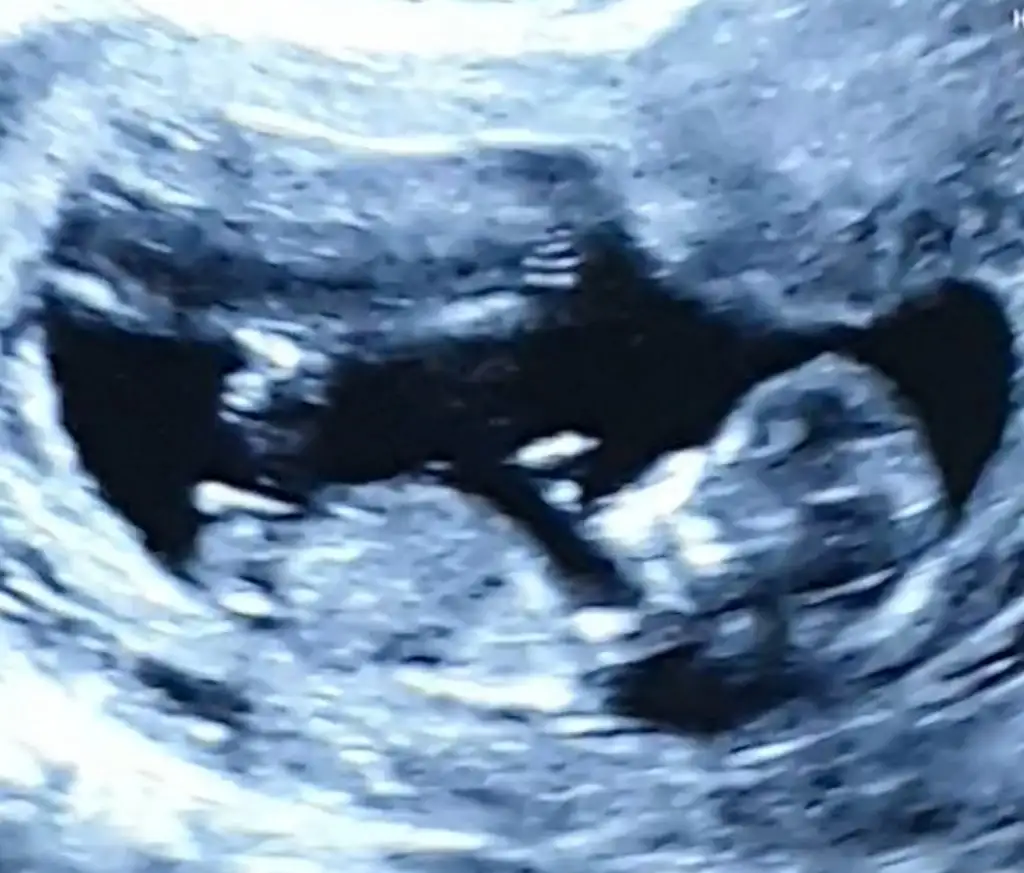

Evet kız görünüyorMerhaba benim usg görüntüm videodan o yüzden net olmayabilir tekrar gönderirim isterseniz. 12+0 doktor muhtemelen kız dedi. Şu beyaz görünen nub mı acaba? Bana da tahminde bulunur musunuz?

Ben de çok kız hissediyorum ama doktorumuz erkek dedi ,bir de sizin tahminlerinizi almak istedim :) siz benzettiniz mi?kız mı bu minnoş

dik olan göbek kordonu sanırım bnce nub paralelBen de çok kız hissediyorum ama doktorumuz erkek dedi ,bir de sizin tahminlerinizi almak istedim :) siz benzettiniz mi?

Ben de öyle görüyorum sanki ,ve hislerim aşırı derecede kız yönünde..ama doktor pipi çıkıntısı gördüğünü söyledi sizlerden duymak istedim birdedik olan göbek kordonu sanırım bnce nub paralel

Kordon orda olmazdik olan göbek kordonu sanırım bnce nub paralel